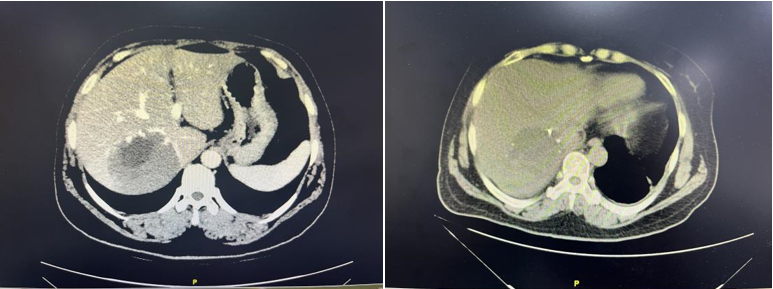

本着一切为了患者的信念,陆朝阳教授团队通过术前3D立体成像技术精确评估,反复推敲设计手术路径,通过术中超声定位,最终在腹部超声科、麻醉科、手术室、护理等团队的合作下,经5小时的奋战,依靠成熟的微创手术技术和丰富的手术经验,仅仅通过腹壁上的6个小孔就实现了腹腔镜下巨大肝血管瘤的微创切除,整个手术出血量不到100ml。术后12小时患者恢复进食,仅36小时就可下地活动,患者术后各项指标恢复良好,术后5天康复出院。

▲图2术前、术后复查CT对比提示肝脏恢复良好